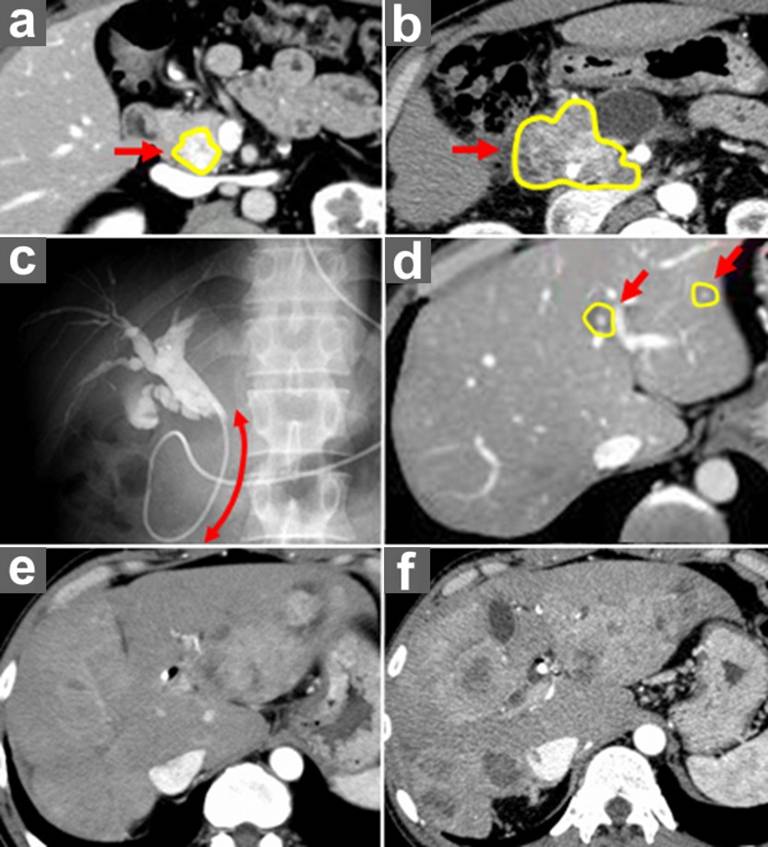

A thirty-nine-year-old man was diagnosed with nonfunctioning P-NET in the pancreatic head, with multiple liver metastases (Figure 1ad). Imaging revealed no extrahepatic metastases, and endoscopic fine-needle aspiration and liver needle biopsy showed well-differentiated GEP-NET G1. The tumor was 2.5 cm in diameter (Figure 1a) and nonfunctioning. Small but multiple metastases were detected in the liver (Figure 1d). He was asymptomatic at that time. We initially intended to control the liver metastases before resection of the primary tumor, because we considered liver metastases as the most important factor in the prognosis. Initially, transarterial chemoembolization (TACE) and transcatheter arterial infusion (TAI) were repeated. Thereafter, systemic chemotherapy and biotherapy were introduced according to follow-up assessments. Unfortunately, imaging assessment at about 10 months later revealed that the liver metastases were partially enlarged, although some were successfully treated. Therefore, these therapies were switched to other regimens, and TACE/TAI, systemic chemotherapies and biotherapies were repeated. Although liver metastases temporarily seemed to be stable (Figure 1e), the primary tumor was extended, even after therapy (Figure 1b). At 3.5 years after initial diagnosis, the primary tumor caused symptoms of pain and obstructive jaundice (Figure 1c). Selective inhibitor of mammalian target of rapamycin (mTOR) was given, and obstructive jaundice was treated by metallic-stent placement. Liver metastases were enlarged (Figure 1f), and there was massive swelling of the para-aortic lymph nodes. Thereafter, palliative therapy was the principal course of action. He finally died at 4.3 years after initial diagnosis.